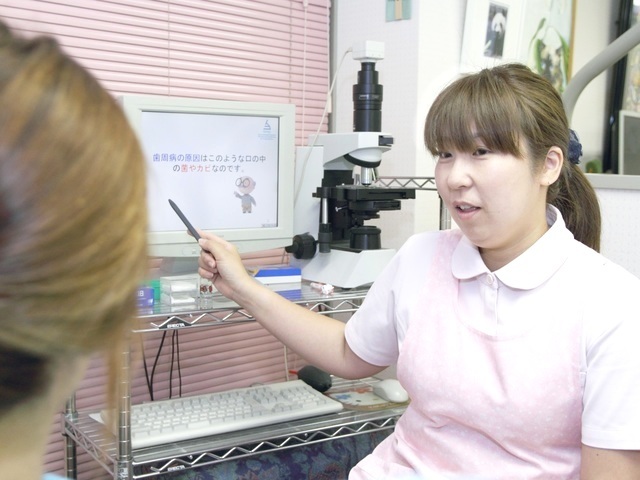

薬で治す歯周病治療を行っています

飲み薬やうがい薬を使って歯周病を治す、【歯周内科治療】を行っています。重度の歯周病でも、歯周外科手術(歯ぐきの手術)をせず治療ができ、痛みがなく患者さまにとって負担が軽い最新の歯周病治療法です。